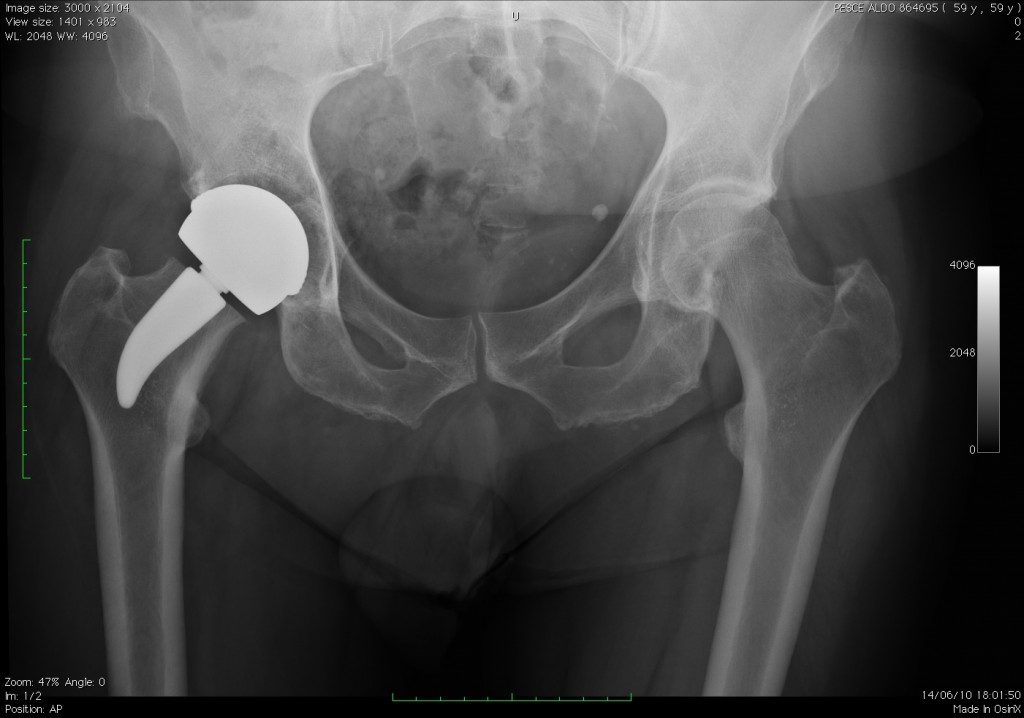

Esempio di impianto con stelo ‘Just’

Iconografia di stelo ‘JUST’